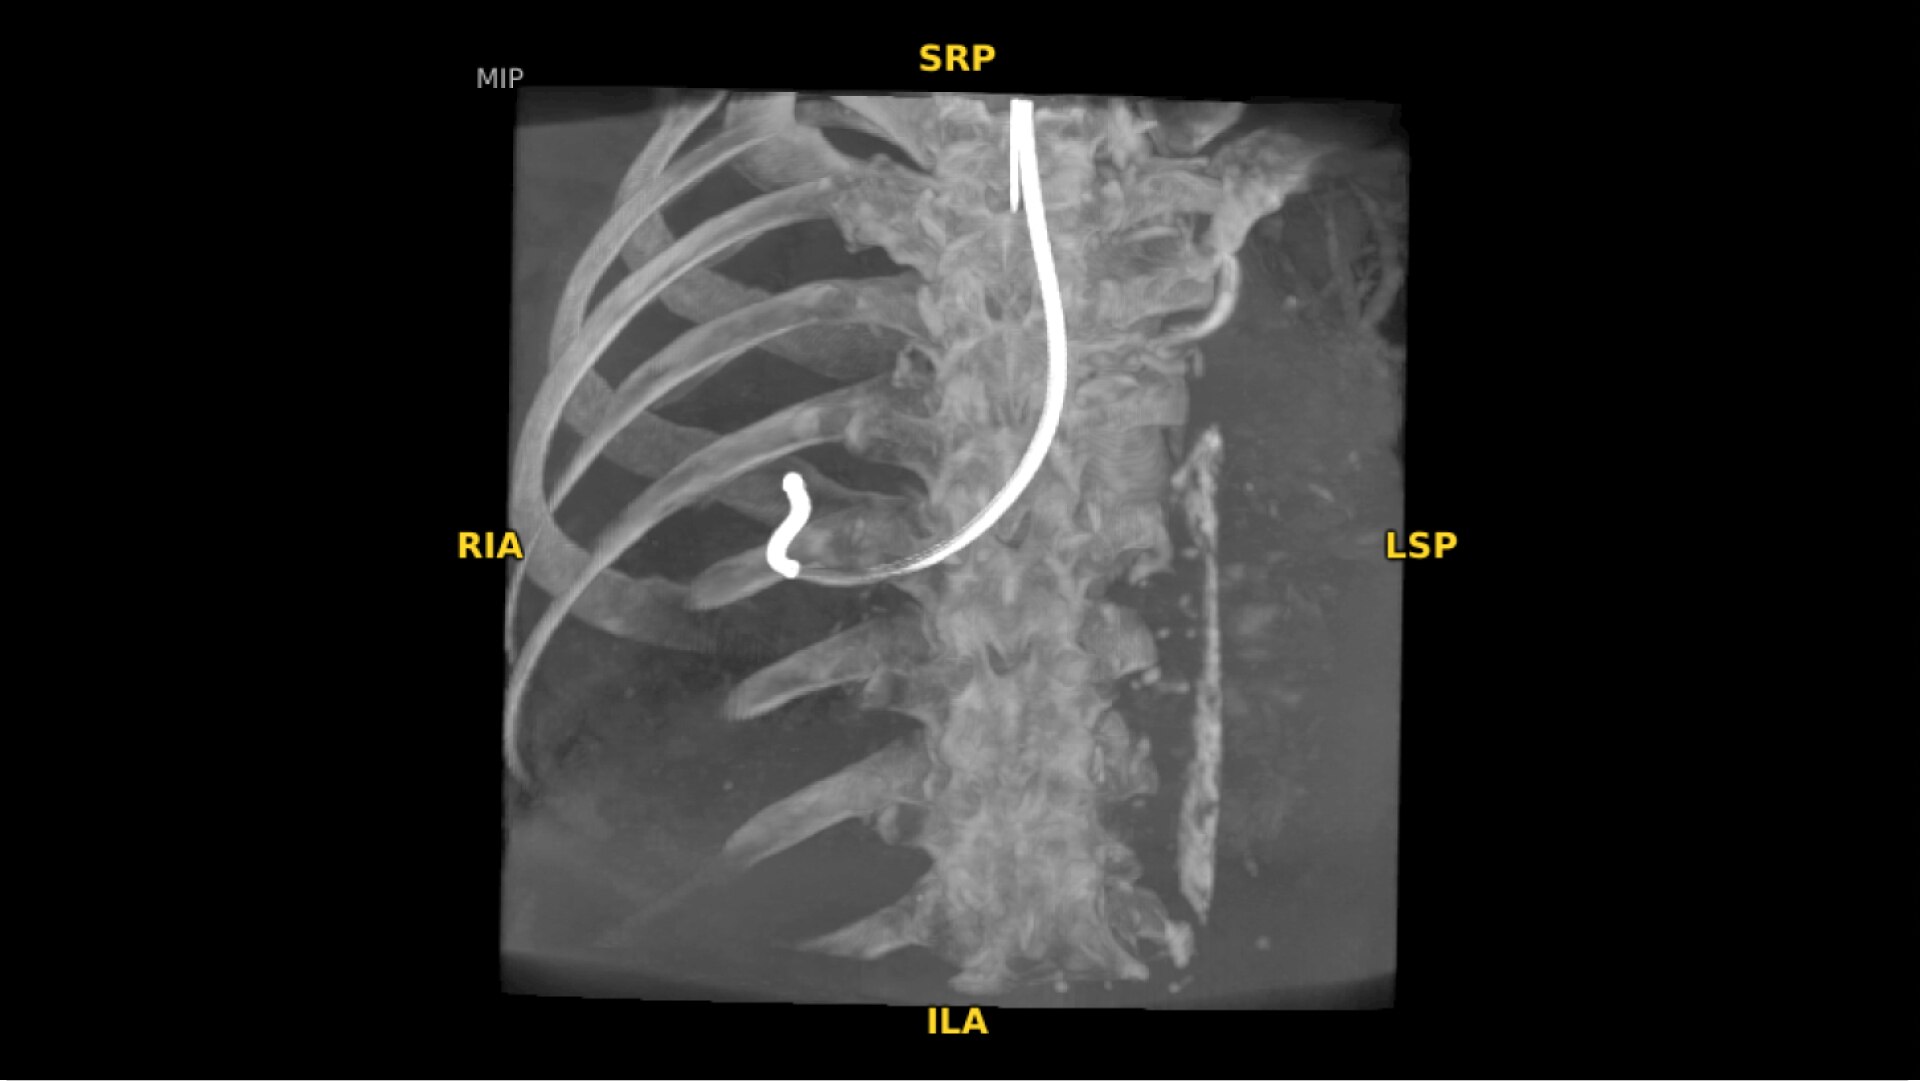

Augmented fluoroscopy aids visualization with ability to select point of interests in the OEC 3D CBCT volume and overlay on live fluoroscopy images. To accommodate patient and equipment positioning, the OEC 3D scan range is also adjustable for a simplified imaging workflow. Features available in Lung Suite application.